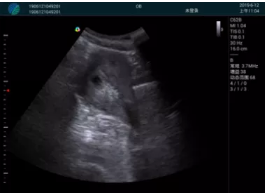

甲狀腺囊性結(jié)節(jié),囊壁鈣化,透聲好

甲狀腺囊性占位